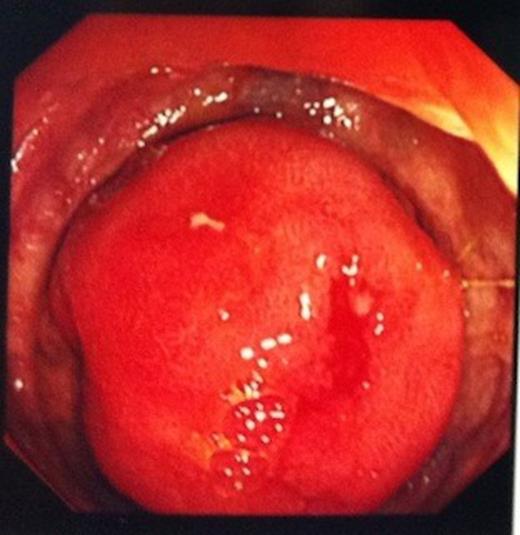

A 74 year old man was referred to our endoscopy unit after a positive faecal occult blood test. He had no preceeding symptoms or history that would place him at increased risk of colorectal cancer. At colonoscopy, excellent views were obtained to the ileocaecal valve (ICV) and appendix orifice, confirming identification of the caecum. With no colonic pathology seen, the endoscopist proceeded to intubate the ICV, as part of his routine practice. A 3cm ileal polyp was identified 5cm proximal to the valve (Figure 1) and biopsies were taken.